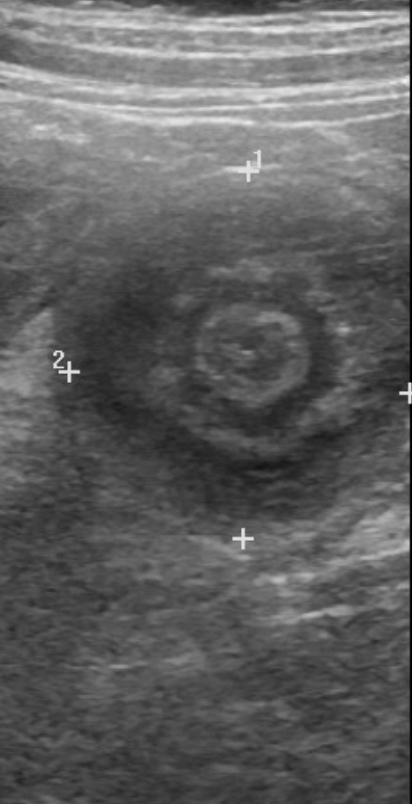

Intussusception

| Diagnostic investigations | If stable and no suspected perforation: USS abdo. sens/spec 98%. Target/doughnut sign; indicative of mesenteric blood flow. |